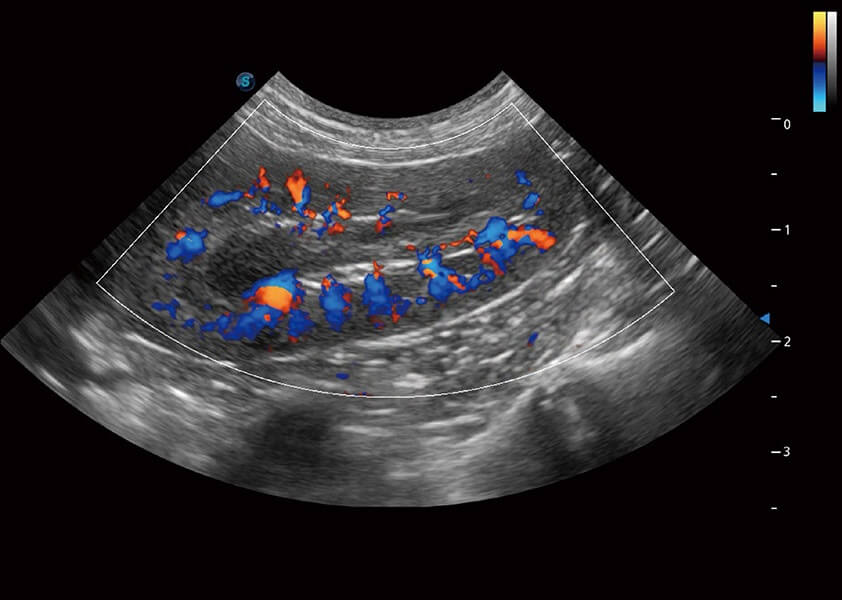

ProPet 60 作为一款高端台式动物超声设备,为动物医生的日常诊断提供了一系列贴合动物临床需求、解决临床实际问题的高级成像功能。凭借全系列高清探头,满足医生对腹部、心脏、生殖、浅表、肌骨等成像的所有需求,切实帮助您提升检查效率,提高诊断信心。

动物是人类最亲密的朋友和最值得信赖的伙伴。DB中国旗舰官方网站也一直致力于探索动物专用的超声影像解决方案。 全新推出的ProPet系列,是DB中国旗舰官方网站在动物超声影像智能化、专业化、精准化的一次跨越式革新。动物不能用言语来表述自己的不适,通过超声影像,ProPet系列搭建了动物医生与不同物种沟通的“桥梁”,为动物医生注入了“治愈之力”。